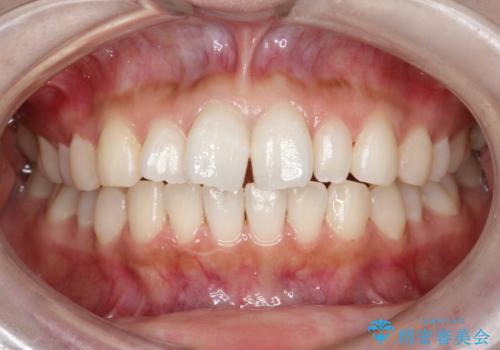

【インビザライン】矮小歯を有する方の治療②

- 前歯の凸凹を主訴に来院されました。

左上の前歯が元々小さいため、前歯の真ん中が揃わないことを伝えた上で矯正治療を開始しています。

スペースを作るために遠心移動ろIPRをおこなて治療を行いました。